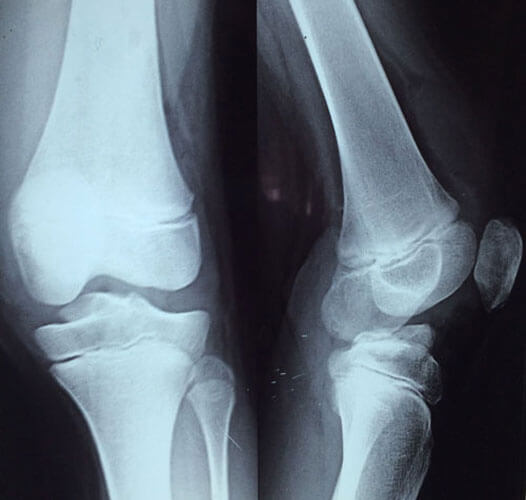

Arthroscopy Surgery